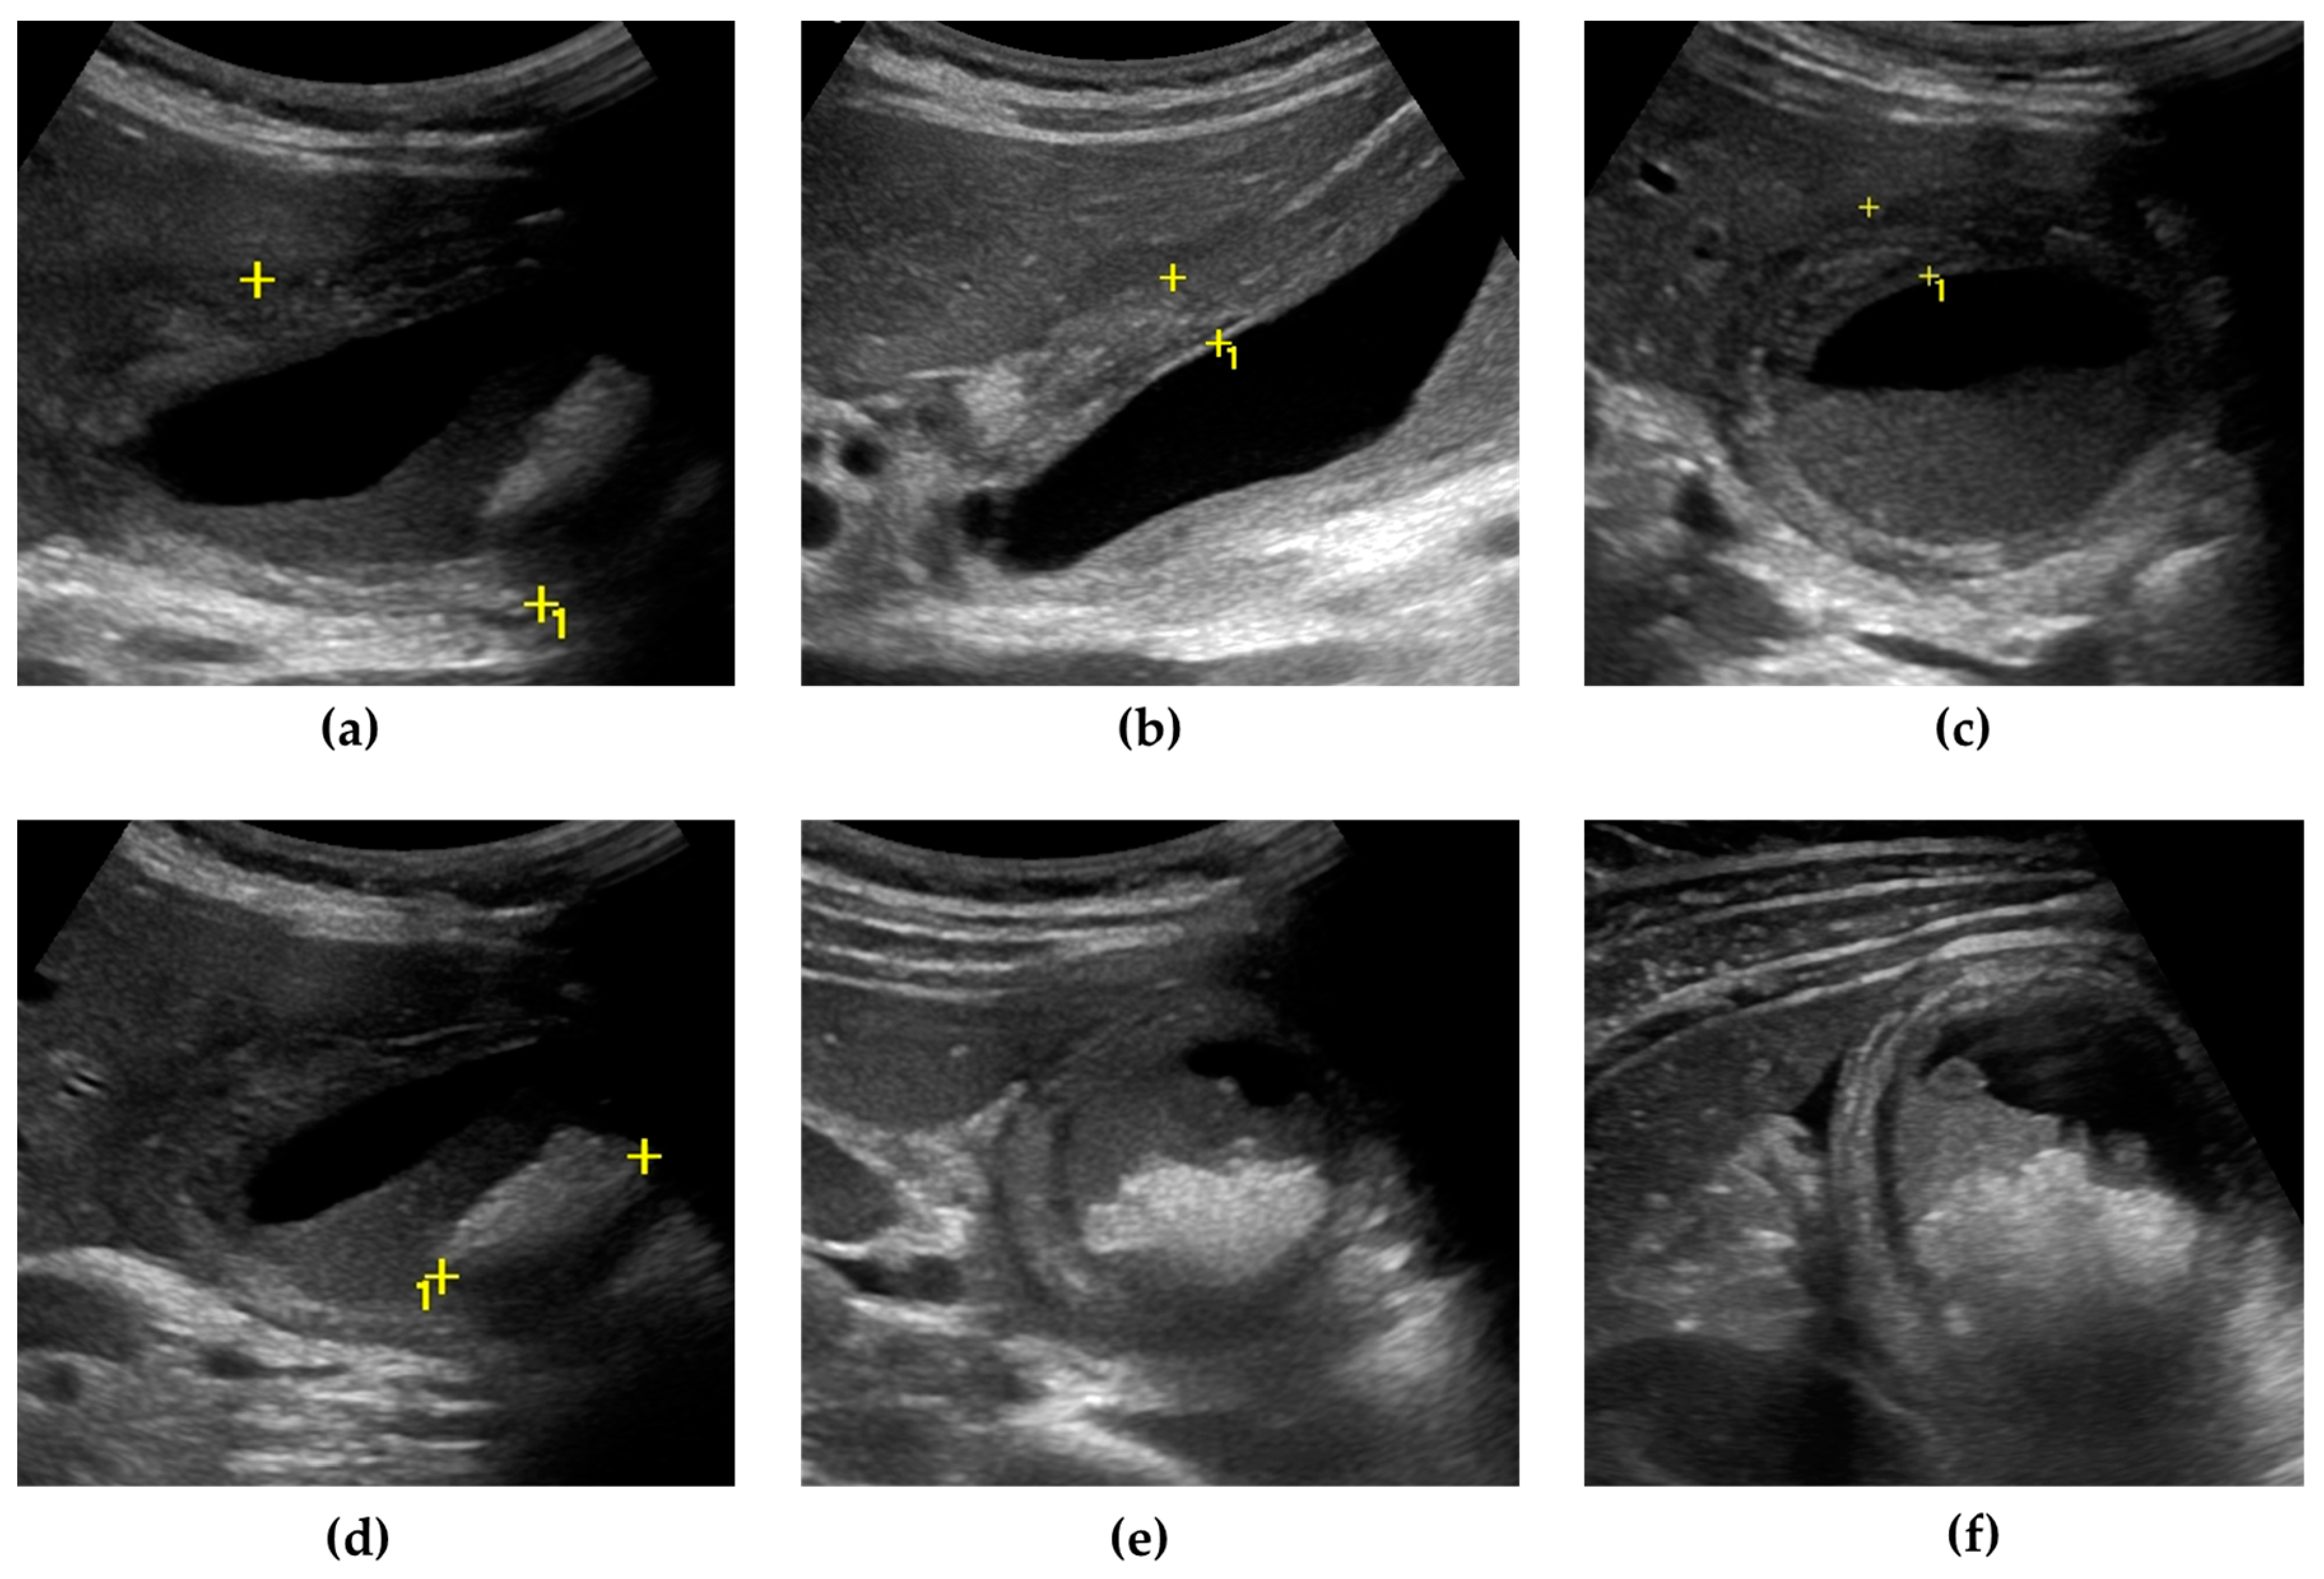

US can also detect AC complications. Gangrenous cholecystitis (Figure 1) is characterized by a thickened and irregular gallbladder wall, sometimes with desquamated mucosa, appearing as an intraluminal flap [36,37]. A defect of the gallbladder wall (“hole sign”) represents the direct visualization of parietal perforation (Figure 2), often communicating with pericholecystic collections or surrounded by hyperechoic mesenteric reactions [37,38]. Additionally, US can be useful in differentiating gallbladder empyema, emphysematous cholecystitis, and a phlegmonous reaction or pericholecystic abscesses [1,39,40].

Figure 1.

Gangrenous cholecystitis. The gallbladder is markedly distended, with an antero-posterior diameter greater than 5 cm (calipers) (a). The gallbladder walls are thickened (up to 10 mm), with a layered appearance, showing multiple striations and alternating hypo/hyperechoic bands (calipers) (b,c). Inside the gallbladder lumen, a significant amount of biliary sludge (non-shadowing echoic material, determining a horizontal fluid–fluid level) surrounds a microlithiasis aggregate, a brighter echoic material with an acoustic posterior shadow (calipers) (d,e). A small triangular fluid collection is present between the gallbladder and liver surface (f).